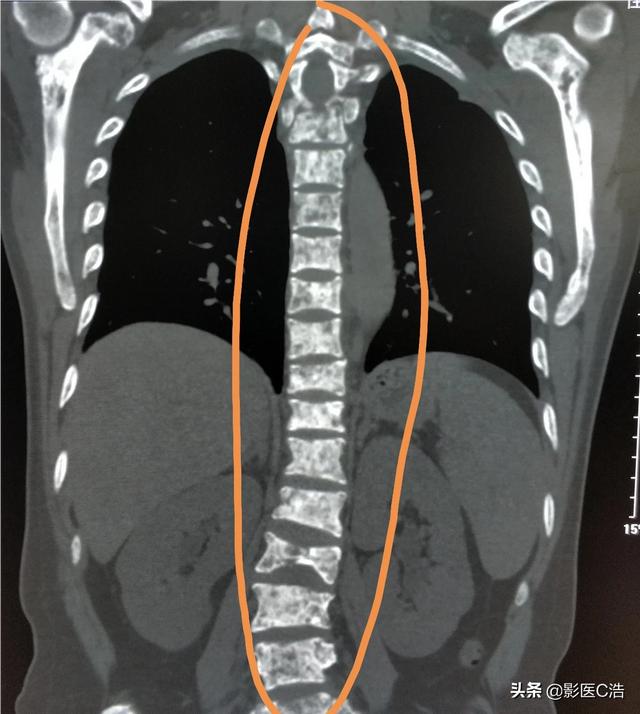

Quel type de douleur doit alerter sur la présence de métastases osseuses ? Les métastases osseuses sont une manifestation fréquente des tumeurs malignes à un stade avancé. La tumeur primaire présente dans d'autres parties du corps se métastase dans les os par les voies sanguines et lymphatiques, formant ainsi des métastases osseuses. Les métastases osseuses signifient que le tissu osseux normal a été détruit et remplacé par du tissu tumoral. Les métastases osseuses peuvent être classées en trois types selon la spécificité de la lésion : le type ostéolytique, le type ostéogénique et le type mixte. Les sites courants de métastases osseuses sont l'os de la diaphyse moyenne (colonne vertébrale et bassin), les côtes et la métaphyse inférieure, l'os de la diaphyse moyenne étant le plus courant, ce qui est lié aux caractéristiques de l'apport sanguin dans cette zone. Comme le montre le cercle ci-dessous, les métastases osseuses sont multiples et la colonne vertébrale est en mauvais état.

Quels sont les symptômes des métastases osseuses ? Le premier symptôme est la douleur. Le site de la métastase osseuse ressentira une douleur due à la destruction de l'os, qui peut ne pas présenter de symptômes évidents ou une douleur intermittente au début, mais comme la tumeur détruit l'os normal de manière progressive et s'aggrave peu à peu, la douleur dans le site métastatique s'aggravera également progressivement. Sur le plan clinique, il arrive que nous rencontrions un cas de douleur osseuse dans une certaine partie du corps, qui résulte d'une métastase osseuse d'une tumeur maligne. Il y a quelque temps, j'ai rencontré un cas, 40 ans, douleur à l'épaule, j'ai pensé à une épaule gelée, j'ai frotté quelques jours d'huile médicinale sans voir d'amélioration, mais de plus en plus de douleur, alors je suis allé à l'hôpital pour un examen, j'ai fait une imagerie par résonance magnétique, l'omoplate a été mangée par un morceau de (tumeur), considérant qu'il s'agissait d'une métastase osseuse, puis j'ai fait un scanner thoracique, un nodule dans le poumon droit, puis j'ai fait une biopsie pour faire la pathologie, qui était une métastase osseuse d'un cancer du poumon. Les informations sont les suivantes.

Sur le site des métastases osseuses, étant donné que le tissu osseux normal est détruit et remplacé par du tissu tumoral et que les cellules tumorales prolifèrent constamment, des ombres de masses de tissus mous peuvent être observées sur de nombreux sites de métastases osseuses, et peuvent être palpées si la masse se trouve dans une zone superficielle. En outre, l'érosion du tissu osseux normal par le tissu tumoral entraîne également la destruction et l'affaiblissement de la structure osseuse normale, de sorte que des fractures peuvent se produire sous l'effet de forces externes normales, appelées fractures pathologiques (figure ci-dessous). Outre la douleur et la fracture pathologique, les métastases au niveau de la colonne vertébrale peuvent également se manifester par une compression des racines nerveuses de la colonne vertébrale avec des symptômes tels qu'une déficience sensorielle, une faiblesse musculaire et, dans certains cas, une hypercalcémie.